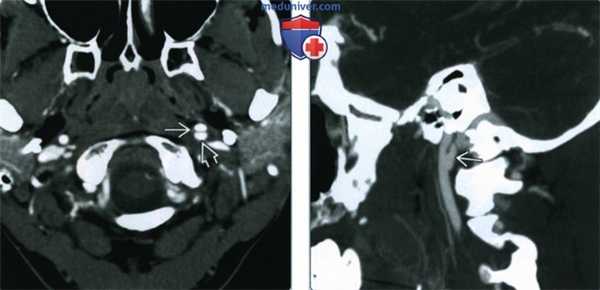

(Слева) КТ с КУ шеи, аксиальная проекция. Циркулярное утолщение стенки общей сонной артерии в области бифуркации. Был выставлен предположительный диагноз каротидинии, симптомы разрешились спустя 36 часов после назначения глюкокортикоидов.

(Справа) КТ с КУ в аксиальной проекции, картина, характерная для острой идиопатической каротидинии. Гомогенное мягкотканное образование, которое заключает в себя дистальный конец левой общей сонной артерии. Выраженного сужения просвета сосуда нет.

2. КТ при острой идиопатической каротидинии:

• Гомогенное утолщение стенки сонной артерии

• Контрастное вещество накапливает плохо или не накапливает вовсе

• Расслоение сонной артерии с ее тромбозом, либо бляшка низкой плотности могут выглядеть точно так же

• Циркулярное утолщение стенки сонной артерии:

о Область бифуркации или дистальная часть общей сонной артерии

о Просвет сосуда обычно не сужен

• МРТ с контрастированием предпочтительнее, чем КТ:

о Интенсивное накопление контраста будет отмечаться только при МРТ

о Накопление контраста при КТ будет слабым

о УЗИ: гипоэхогенное мягкотканное образование в области бифуркации или дистальной части общей сонной артерии

(Справа) КТ с КУ в аксиальной проекции, картина, характерная для острой идиопатической каротидинии. Гомогенное мягкотканное образование, которое заключает в себя дистальный конец левой общей сонной артерии. Выраженного сужения просвета сосуда нет. (Слева) МРТ Т1ВИ FS с КУ, аксиальный срез. Пациента беспокоит болезненность при пальпации области сонной артерии. Стенка общей сонной артерии утолщена, интенсивно накапливает контраст. Такие признаки характерны для каротидинии. Обратите внимание, что просвет сосуда не сужен.